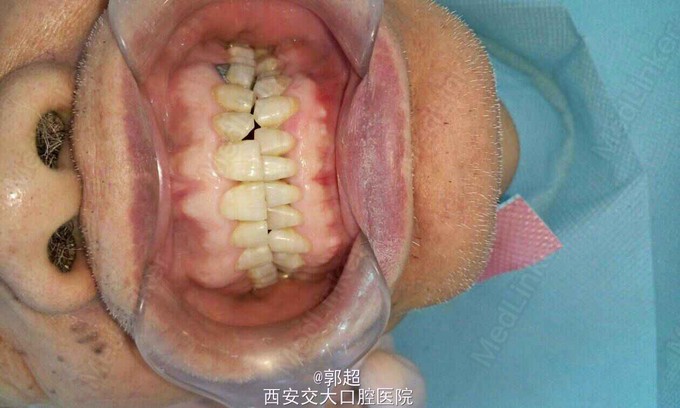

右下后牙拔除4月要求修复。 男,80岁,既往体健,半年前因咬硬物致使右下后牙劈裂至根中1/3,于外院拔除。

46缺失,牙槽脊轻度吸收,咬合间隙可。咬合异常,一侧后牙咬紧,对侧开牙合,下颌正中咬合时,两侧牙列颊尖均有1mm间隙,反复检查纠正还是如此。

由于患者耳聋交流不畅,家属心情急切,没有详细询问其咀嚼习惯及其他病史。 求教各位,一般这类咬合是怎么形成的b遇到这类病人都是怎么处理的?戴牙后咬合怎么调整?咬合记录?